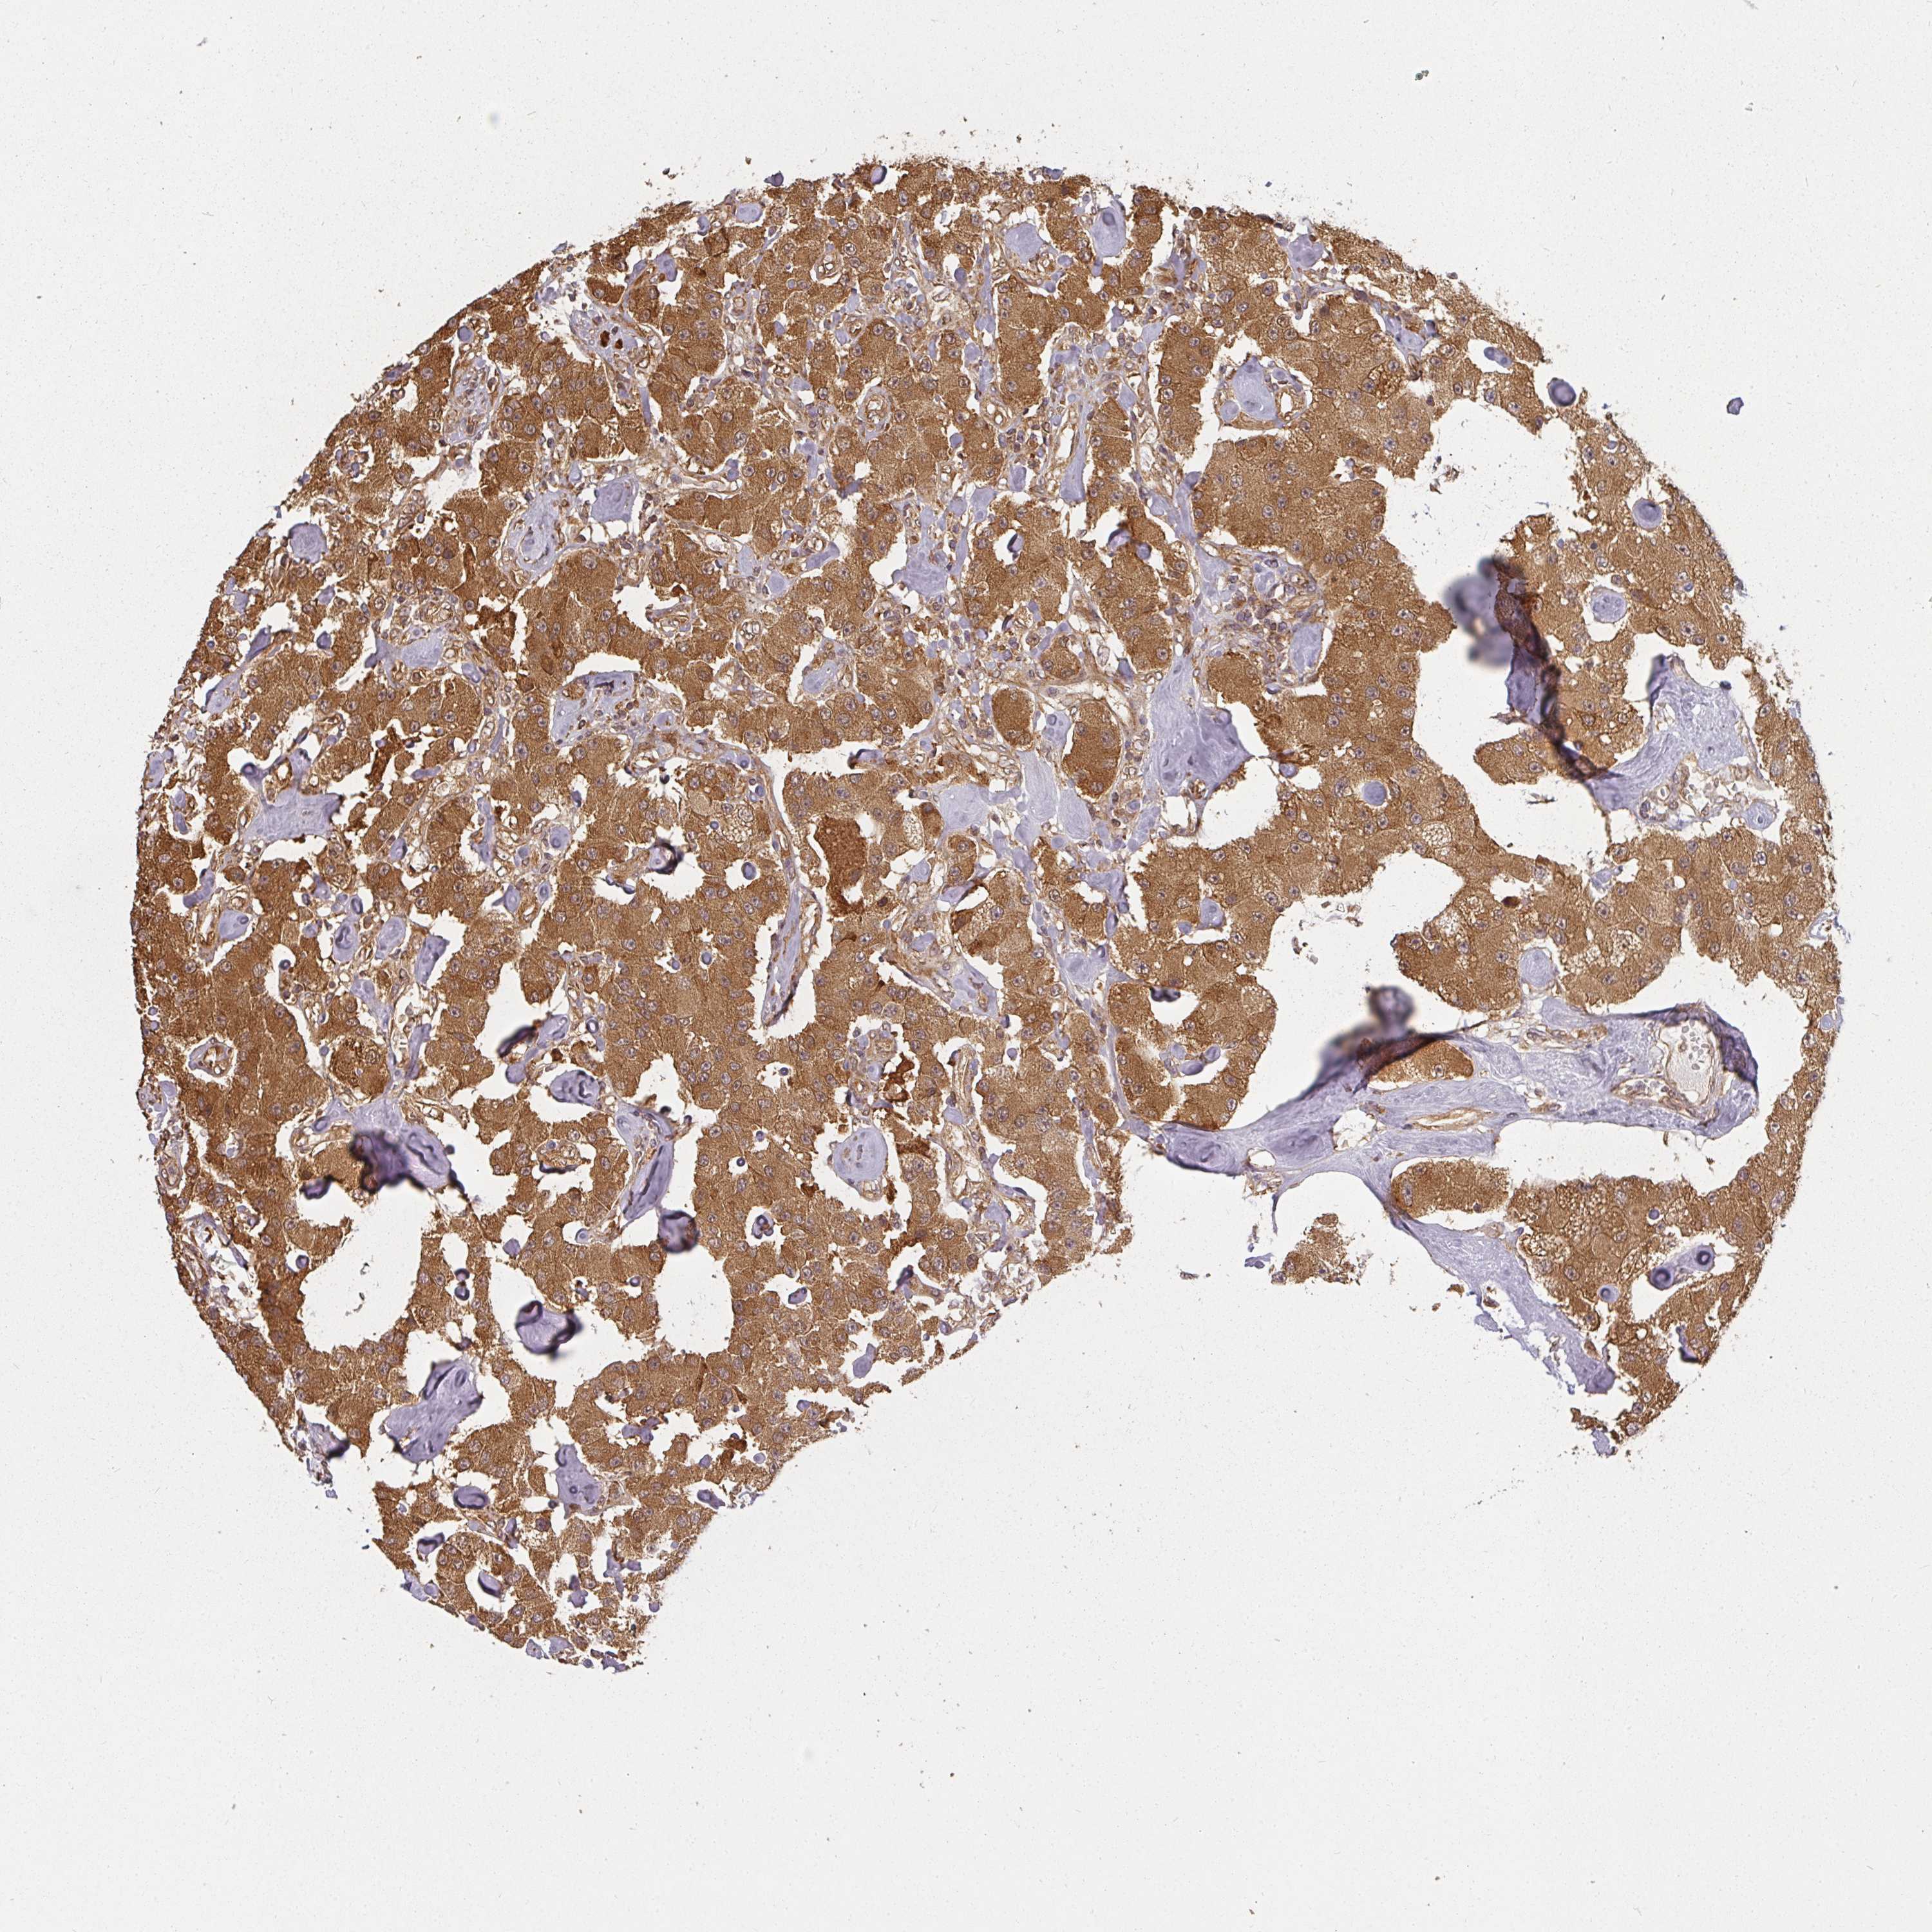

CARCINOID - Protein expressioni

A mouse-over function shows sample information and annotation data. Click on an image to view it in a full screen mode. Samples can be filtered based on level of antibody staining by selecting one or several of the following categories: high, medium, low and not detected. The assay and annotation is described here.

Each image is clickable and will lead to virtual microscopy that enables deeper exploration of all samples and also displays staining intensity scores, fraction scores and subcellular localization as well as patient and tissue information for each sample.

Antibody HPA038467

Antibody CAB017183

Staining

High

Strong

>75%

Location

Cytoplasmic/membranous

Carcinoid, malignant, NOS